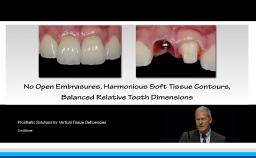

Part one of a two-part presentation gives a comprehensive overview of how to treat complex cases using an interdisciplinary approach in implant dentistry. From the prosthodontist’s point of view, the workflow starts with careful prosthetic planning by the use of wax-ups or set-ups, and in some cases orthodontic pretreatment is indicated. This lecture demonstrates how the prosthetic planning is then transferred by surgical templates to facilitate the correct 3D prosthodontically driven implant placement. In this workflow, the provisional prosthesis conditions the soft tissue in order to optimize esthetics prior to finalizing the prosthetic rehabilitation. This lecture includes a series of ‘Prosthetic Rules’ to serve as benchmarks for effective prosthodontically driven treatment.

- describe the workflow of careful prosthetic planning, surgical templates during implant placement, provisional prosthesis with soft tissue conditioning, and final rehabilitation